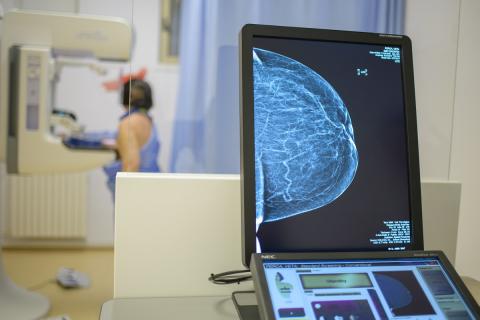

Mamografia este o radiografie specială a sânului, o examinare sigură, fiind considerată cea mai importantă şi de acurateţe metodă în detectarea cancerului mamar.

În cazul mamografului analog imaginile sunt printate pe film însă, la mamograful digital găsim numeroase beneficii:

+ Imaginea sânului este la o calitate mult superioară;

+ Doză de iradieră cu 40% mai mică decât în cazul mamografului analogic şi rezoluţie mai mare;